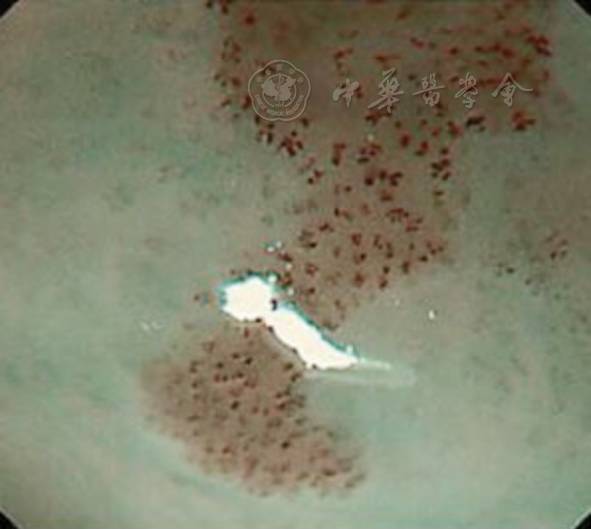

利用IPCL诊断食管病变时分为两个步骤:首先找到NBI下呈褐色变化的区域,或者是碘染色的不染区;第二步使用放大内镜观察病灶,评估IPCL类型。IPCL可分为5型(图5),其变化包括扩张、弯曲、不均匀、管径变化等特征,据此可初步诊断病变的性质,从正常食管黏膜、炎症、异型增生到癌,内镜下图像见图6。其中从IPCL Ⅱ型到Ⅴ-2型的变化发生在黏膜层,能够保持原IPCL的结构,变化主要发生在垂直平面;Ⅴ-3型则表现为不规则的IPCL原结构进一步破坏,呈水平面变化;在ⅤN型中原IPCL结构完全破坏,粗大管径的新生肿瘤血管呈水平方向分布。Ⅴ-3和ⅤN型的区别在于肿瘤血管的管径,ⅤN型肿瘤血管的管径约为Ⅴ-3型的10倍,提示肿瘤的浸润深度不同。

图6 上皮内状微血管襻(IPCL)各分型的内镜下表现 6A~6D 分别为IPCL Ⅰ~Ⅳ型 6E~6H 分别为IPCL Ⅴ-1、Ⅴ-2、Ⅴ-3和ⅤN型

不同的IPCL分型代表不同的病变和浸润深度,IPCL Ⅰ型见于正常食管黏膜,IPCL Ⅱ型见于炎性病变,IPCL Ⅲ型见于慢性食管炎等,IPCL Ⅳ型见于HGIN,IPCLⅤ-1型及Ⅴ-2型分别见于M1期癌和M2期癌,IPCL Ⅴ-3型主要见于M3期癌、SM1期癌或浸润更深的癌,IPCL ⅤN型主要见于SM2期癌或浸润更深的癌,详见图5。通过IPCL分型来预测肿瘤的浸润深度的准确率比较高,Goda等报道显示,通过IPCL分型来预测黏膜内癌和黏膜下层癌的敏感性和特异性分别为78%和95%;Inoue等报道显示,对于IPCL Ⅳ型病变的诊断准确率为80%。